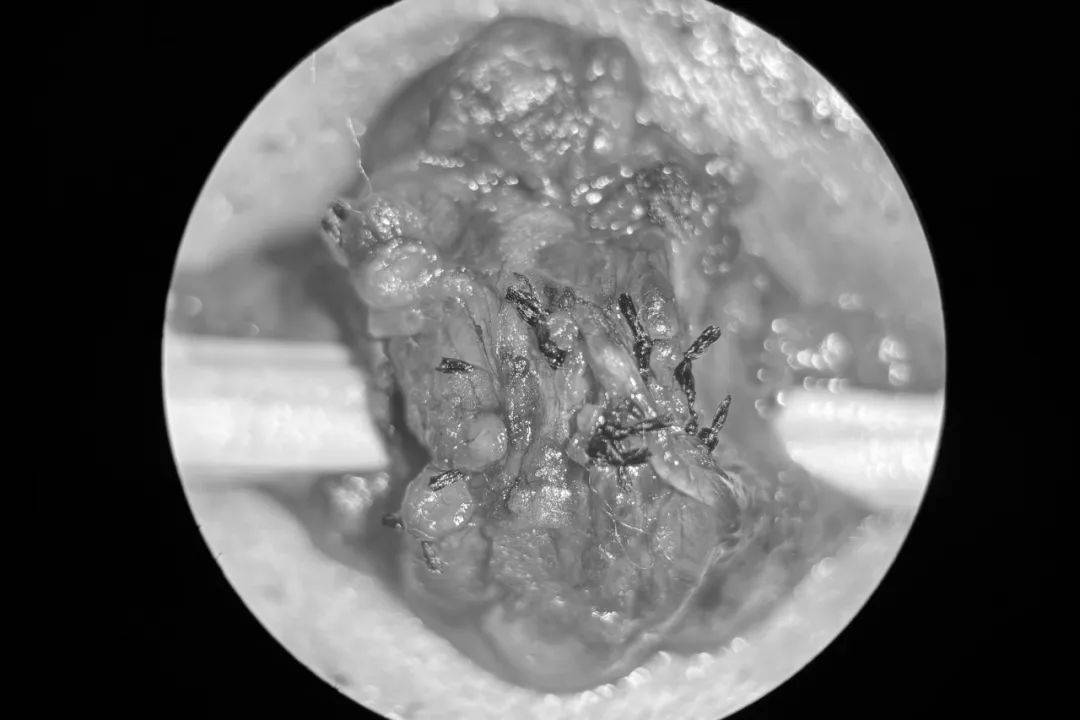

精索静脉曲张显微镜手术

引起精液质量下降的,以及出现睾丸萎缩的,都可以考虑行该手术治疗该手术在显微镜的放大作用下操作,具有创伤小出血少手术风险小静脉结扎彻底,可以良好的保护精索内动脉和淋巴管,术后阴囊水肿等并发症少,复发率低,精液质量改善明...